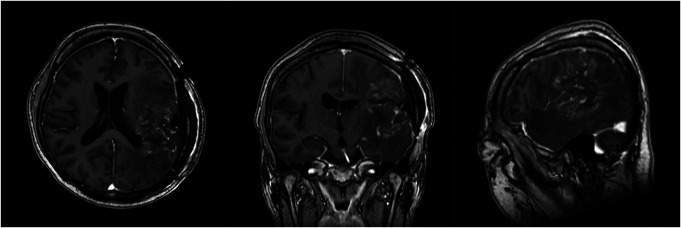

Clinical presentation: A 50-year-old, right-handed woman presented with recurrent glioblastoma invading her left superior temporal gyrus and inferior parietal lobule. She had severe aphasia, as she could barely verbalize her own name. However, we noticed that she could sing nursery rhymes with simple melodies and applied her singing ability as an axis of awake surgery. During awake surgery, she continuously sang simple songs to detect language dysfunction. As a result, 90% of the tumor was resected, preserving her language function and allowing for improvement. She was discharged 9 days after surgery without further neurological deterioration.